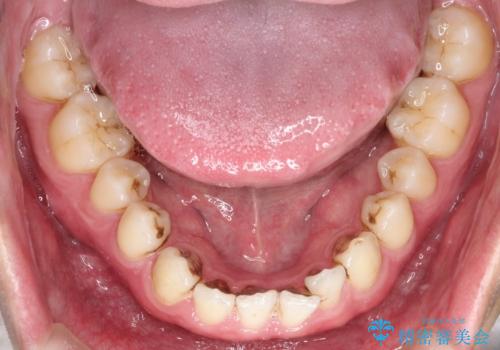

【インビザライン】前歯の隙間を治したい。

- 前歯の隙間を主訴に来院されました。

インビザラインにて治療しました。

ディープバイトも改善でき患者さんも満足されていました。

前歯の隙間だけを閉じる治療を行うだけでは、噛み合わせが悪くなるためディープバイトも改善が必要です。